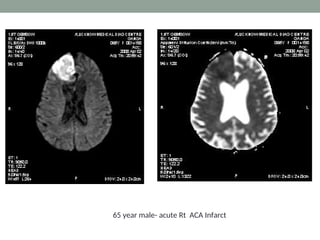

65 year male- acute Rt ACA Infarct

Apparent Diffusion Coefficient •It is a measure of diffusion • Calculated by acquiring two or more images with a different gradient duration and amplitude • The lower ADC measurements seen with early ischemia

• 30.

• The ADCmay be useful for estimating the lesion age and distinguishing acute from subacute DWI lesions. • Acute ischemic lesions can be divided into hyperacute lesions (low ADC and DWI-positive) and subacute lesions (normalized ADC). • Chronic lesions can be differentiated from acute lesions by normalization of ADC and DWI.

• 31.

65 year male-acute Rt ACA Infarct